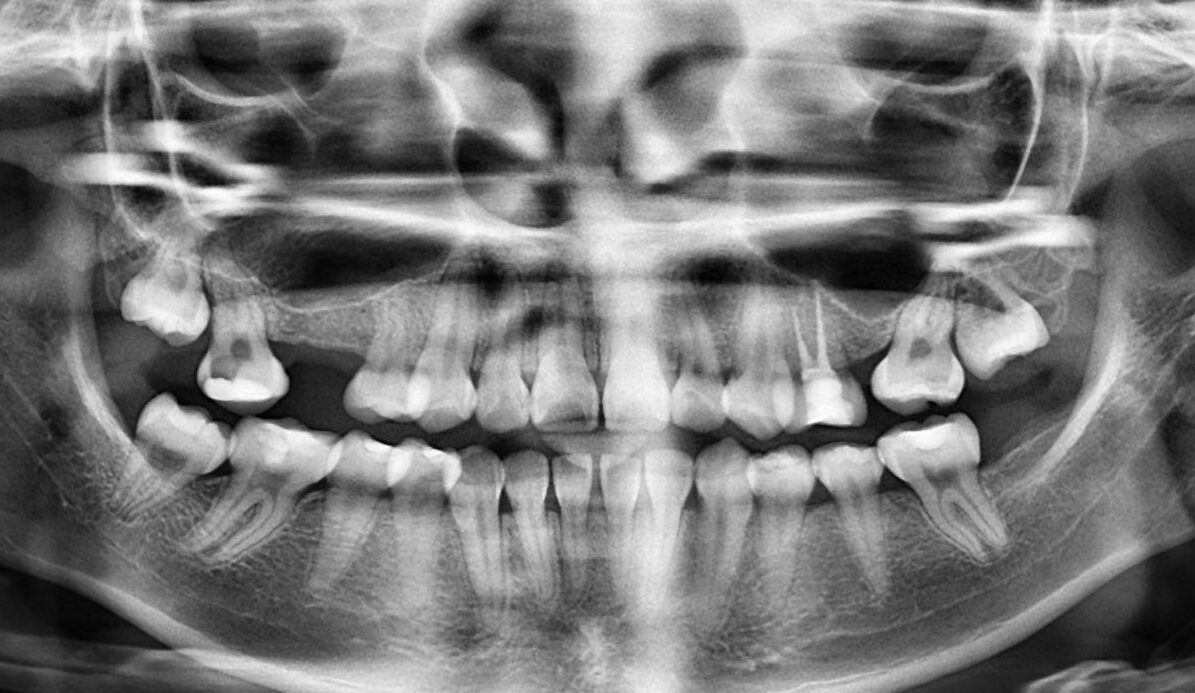

1.  What option cannot be selected for this panoramic X ray?